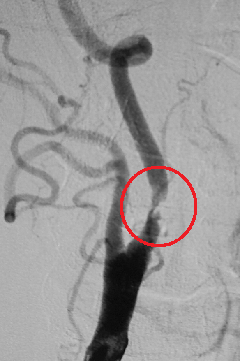

(下図)内頸動脈狭窄症に対して頸動脈ステント留置術を施行しました。良好な拡張が得られています。

頸動脈狭窄症、〇が狭窄している部分

頸動脈ステント留置術後